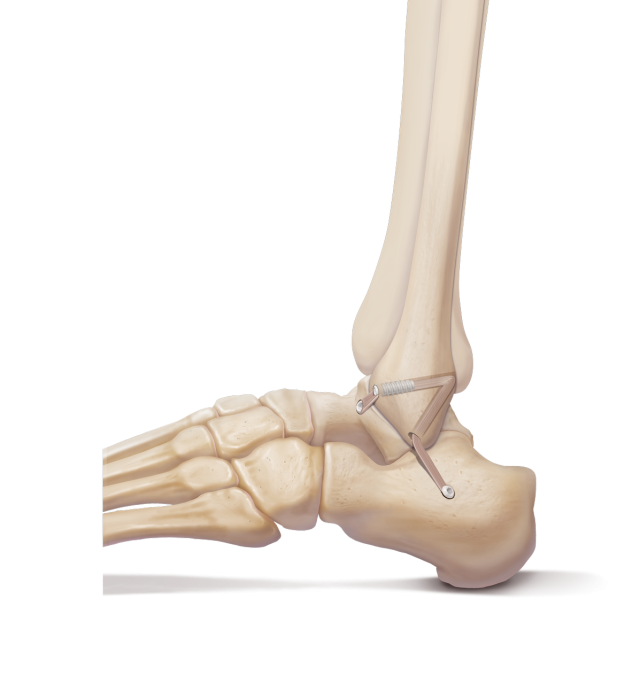

Sind beide Bandanteile defekt, werden beide durch ein Kunstband ersetzt.

Dieses wird dann an Stelle der ursprünglichen Bandstrukturen eingebracht und in eigens gebohrten Knochentunneln mittels Implantaten fixiert.P ostopertiv ist die Verwendung einer Sprunggelenksschiene und für 3 Wochen die Verwendung von Unterarmstützkrücken notwendig.